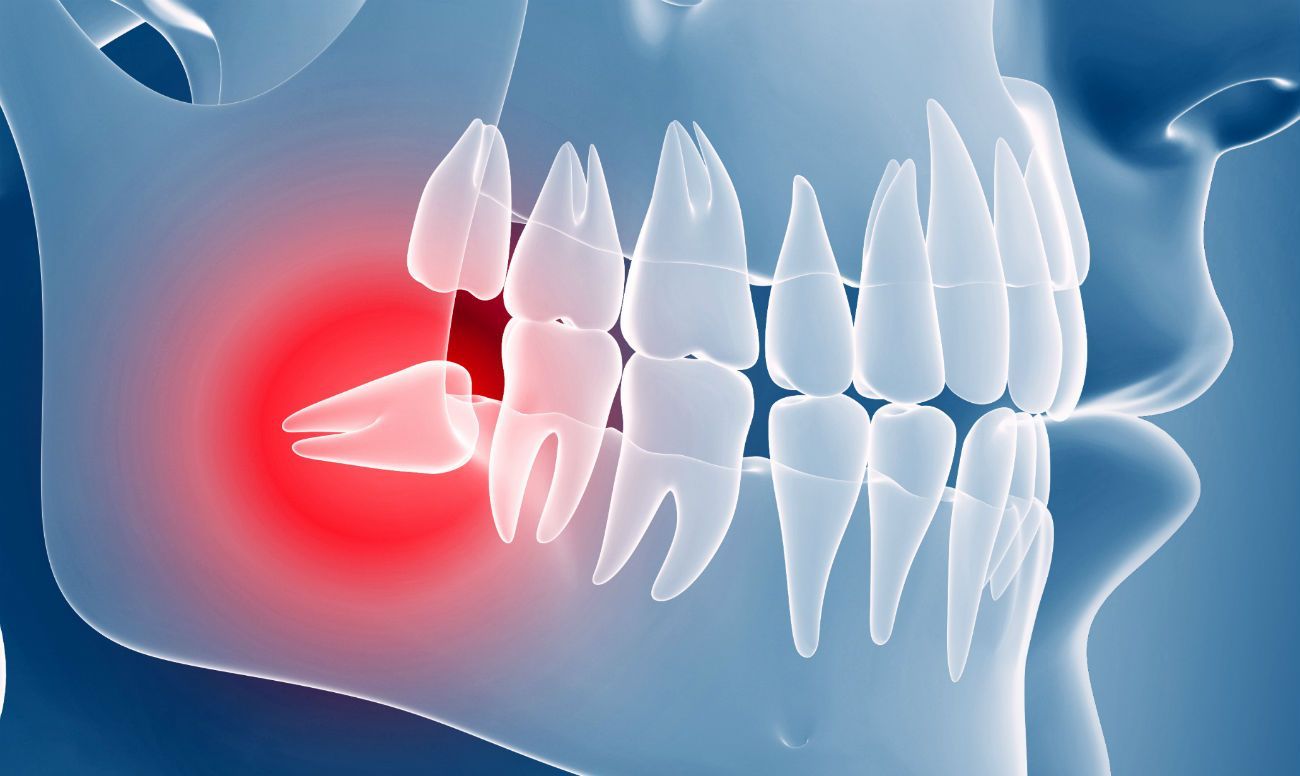

Перед вмешательством анализируем положение зуба по снимкам,

оцениваем строение корней и состояние костной ткани,

чтобы выбрать максимально безопасный и щадящий метод удаления.